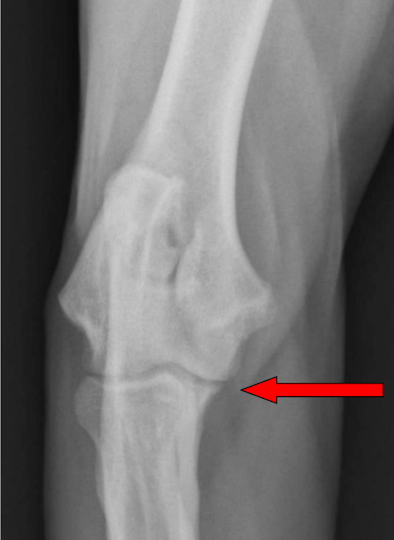

What is the arrow pointing to?

osteophyte on the medial coronoid process in elbow DJD